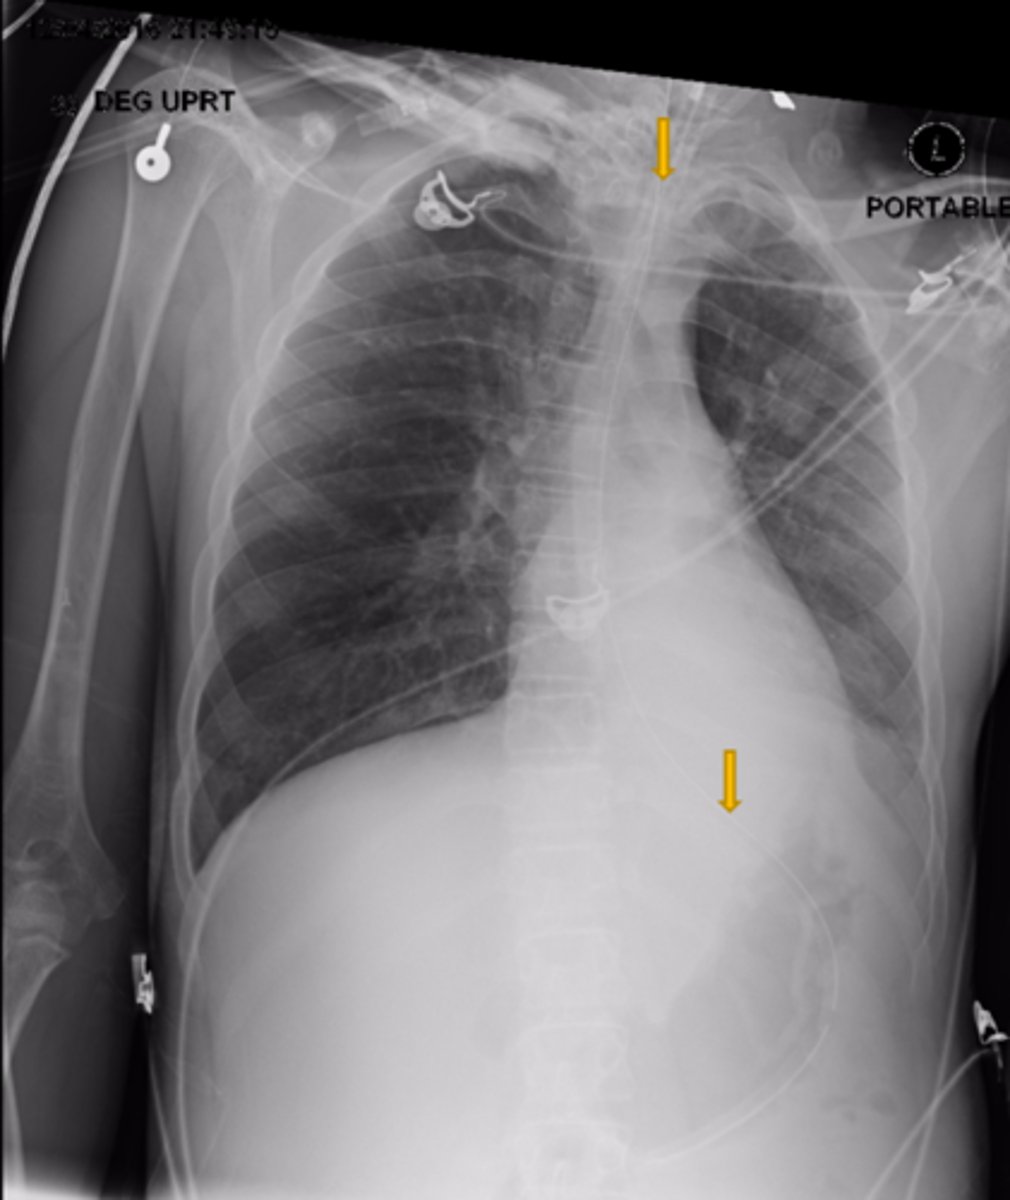

Is this patient rotated?

Yes

Is the Cardiac/Thoracic ratio normal?

Possible CHF (presence of Kerley B lines)

What does the chest film show?

NG OG

What is the structure the yellow arrows are pointing at?

No

Is this a high-quality film?